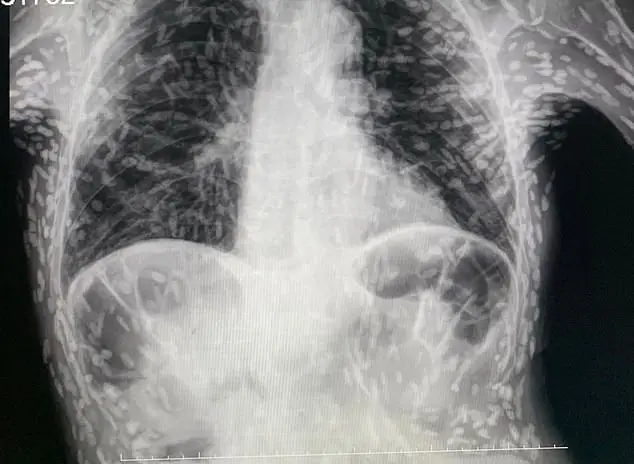

A horrifying x-ray of the discovery was shared on Twitter by Dr Vitor Borin P. de Souza, a practitioner at the Hospital das Clínicas Botucatu in São Paulo, Brazil.

Each of the white dots on the horrifying x-ray image represents a cyst and the calcified remains of a parasite.

Cysts can take months or even years to develop after the ingestion of the tapeworm eggs eggs but can be removed easily through surgery or medication.

"These lesions are calcified so they are not viable cysticerci (tapeworm larvae)."